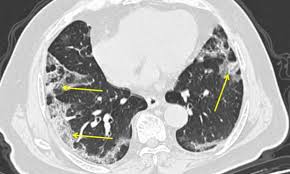

Комп’ютерна томографія та рентген внесені до пакету послуг для пацієнтів з COVID-19 і мають бути безкоштовними.

«В нас комп’ютерна томографія та рентген внесені до ковідного пакету. Якщо є відповідне направлення сімейного лікаря або лікуючого лікаря, то громадянам ця послуга надається безоплатно, тобто за це сплачує держава», — розповів Степанов.